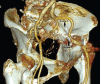

Case report: We present this challenging and unique case of a 64-year-old female patient where the acetabular component screw was found to be adherent to the external iliac vessels, with vascular injury imminent. During revision surgery, the iliac vessels were first released free of all adhesions with the intrapelvis screw using an ilioinguinal incision and retroperitoneal approach. The prosthesis was removed using a posterior approach to the hip joint. Definitive surgery was performed after 2 weeks.

Conclusion: Surgeons should be cognizant of the possibility of an avulsion vascular injury in revision cases having intrapelvic screws or implants. The proximity of such an implant with the intrapelvic vasculature must be confirmed preoperatively. Management should be individualized. Dual approach and staged procedure help in a favorable outcome. Vascular injury, revision total hip arthroplasty, screw abutting iliac vessel, external iliac vessel, computed tomographic angiography.